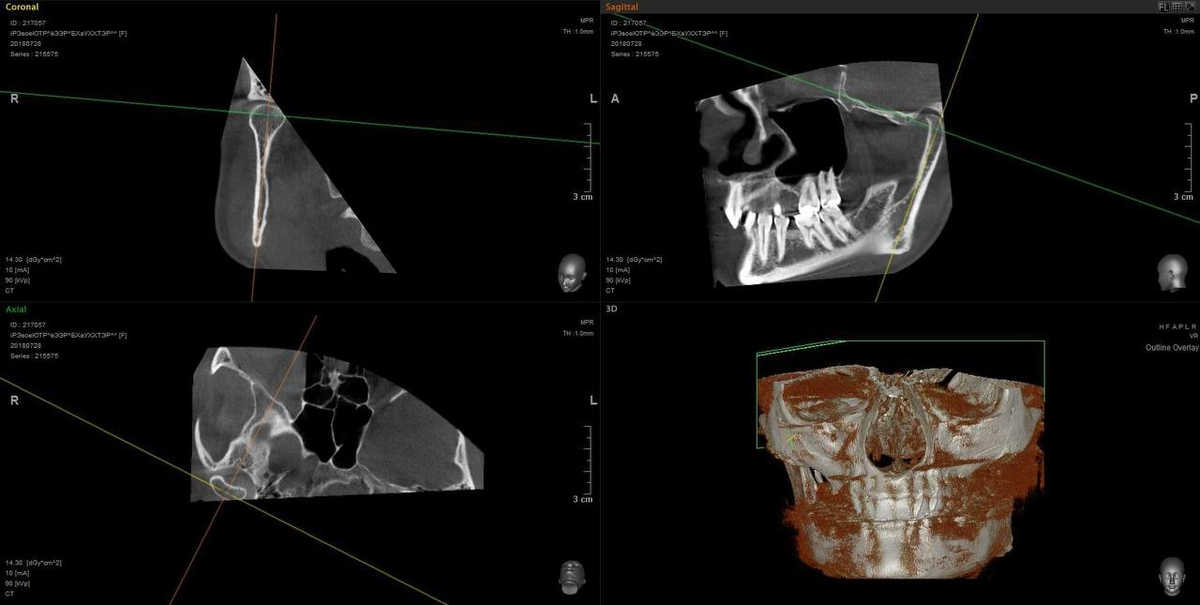

Была поставлена задача расслабить очень сильные жевательные мышцы и вывести сустав из компрессии, поэтому был сплинт в цс, потом прямые накладки и брекеты для освобождения пространства под имплантацию в зоне отсутствующих Зубов

После ортодонтии пациент перешел к ортопеду.

Была проведена аксиография в новом положении челюсти.